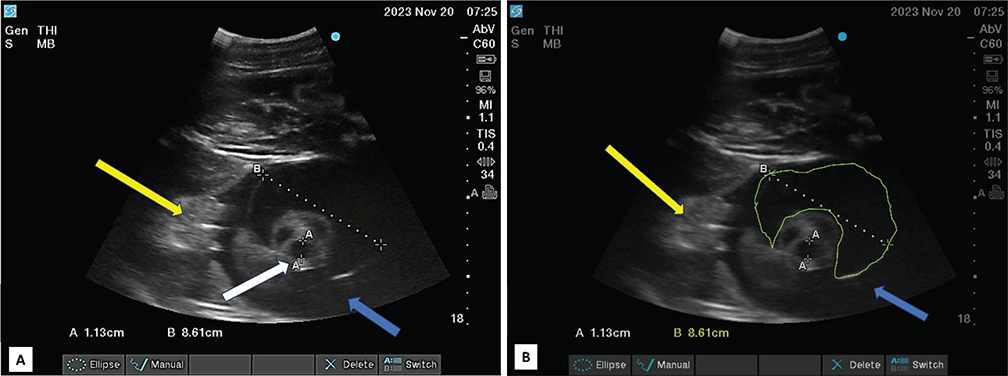

Five days after initial evaluation, the mare appeared to have a wider ventral distribution of abdominal distension and was referred due to concern for impending body wall injury. Altrenogest was discontinued and mare was admitted to the referral hospital on day 230 of pregnancy. Physical examination revealed marked abdominal distension and a plaque of ventral abdominal edema (Figure 1). Transrectal palpation and ultrasonography revealed domed gravid uterus extending well above mare’s pubic level. The CTUP was 0.6 cm (considered normal for this stage of pregnancy).16 Transabdominal ultrasonography revealed turgid amniotic membrane, lacking undulations (Figure 2), suggesting increased intra-amniotic fluid pressure. The largest umbilical vessel within the amniotic cavity was 1.13 cm in diameter (Figure 3A); fetal urachus had increased luminal diameter (Figure 3B). Fetal bladder measured 6 x 5 cm and was distended with anechoic fluid. Doppler was used to identify the urachus by lack of blood flow compared to umbilical vessels (Figure 4). Fetal heart rate was 90 beats per minute and pericardial effusion was suspected due to the appearance of hypoechoic fluid around beating heart muscle. Again, the fetus’s mouth was open. Additionally, ultrasonography of mare’s ventral abdomen revealed marked subcutaneous edema, consistent with impaired lymphatic and venous drainage secondary to gravid uterus weight. A presumptive diagnosis of hydrops was made based on these clinical findings. Termination of pregnancy and induction of parturition was elected to salvage the mare.

Figure 3. Transabdominal ultrasonographic image of umbilical cord structures within the amniotic cavity: A. diameter of largest umbilical vessel (white arrow); B. diameter of urachus (yellow line); mammary gland of filly fetus (yellow arrow) and amniotic cavity (blue arrow).